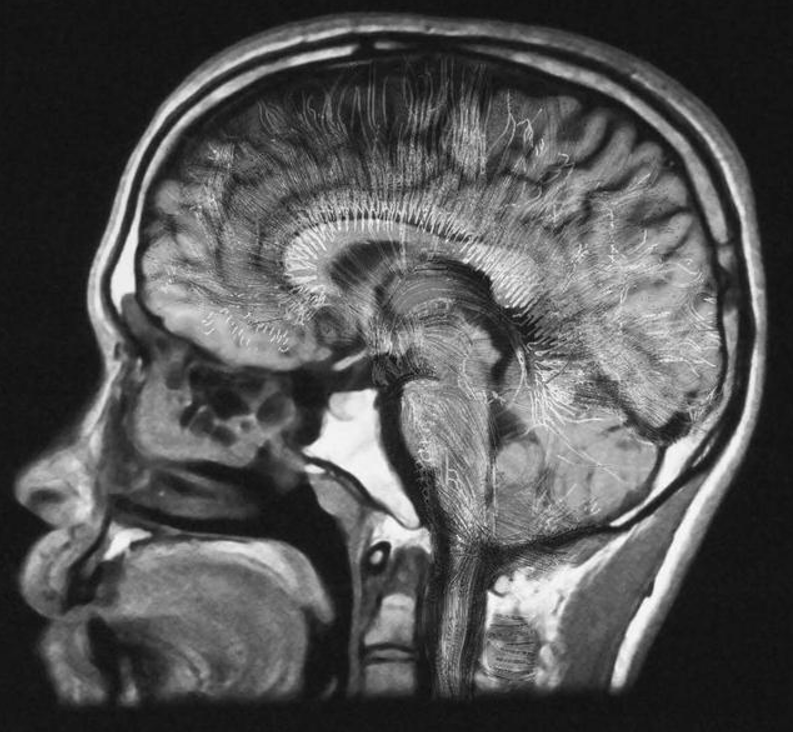

至于大脑如何维持我们的思想和意识,我们仍然知之甚少。不过随着成像技术的进步,在一定程度上揭示了大脑不同区域的神经元如何在不同的刺激下激发放电,就像圣诞树上的灯一样。

上面说的是理解神经元运行方式的简单部分。而困难的部分,则是了解活跃的神经元如何共同创造出「我们是谁」的感觉的。也就是说,生物电活动和血液流动,是如何转化为自我意识的。